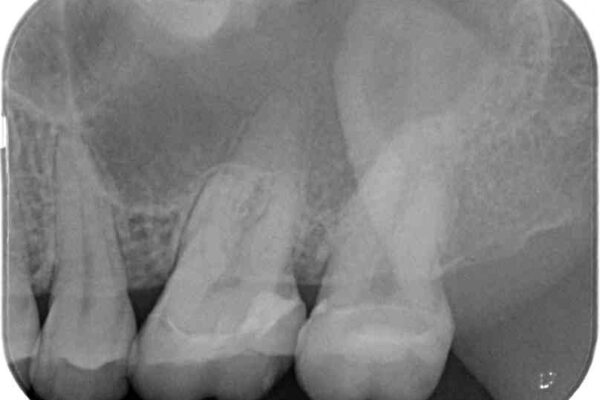

レントゲン写真から、神経組織近くにまで大きな修復物が認められました。

叩いたり、冷熱や電気刺激によるテストを行ったりとしましたが、炎症の状態は芳しくなく、根管治療を行う前提で処置を行うこととしました。

強い咬合力を負担する第一大臼歯であるため、根管治療後は速やかにオールセラミッククラウンにて補綴治療を行うこととしました。

治療途中

• 奥歯がズキズキと痛む 奥歯の虫歯治療 治療途中画像